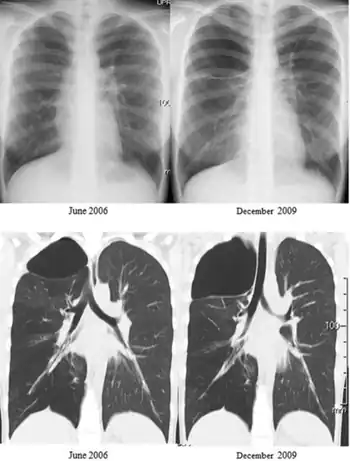

Swyer–James syndrome (SJS) is a disease of the lungs, characterized by a small lung or part of lung.[1] Typical symptoms are of recurrent respiratory tract infections, but some have no symptoms.[2]

Swyer–James syndrome is a manifestation of postinfectious obliterative bronchiolitis.[2] In SJS, the involved lung or portion of the lung does not grow normally and is slightly smaller than the opposite lung.[3] The characteristic radiographic appearance is that of pulmonary hyperlucency, caused by overdistention of the alveoli in conjunction with diminished arterial flow.[4][5] and has been linked to adenovirus type 21, a type of adenovirus infection.[6]

In appearance Swyer–James normally leaves shadowing in a CT scan in the upper lobar regions of one or (rarely) both lungs. People with the illness operate in much the same way as patients with mild bronchiectasis. As a result, the illness can go undiagnosed for some time. With current pharmaceutical developments, the prognosis is good for sufferers of the illness to lead normal and healthy lives.